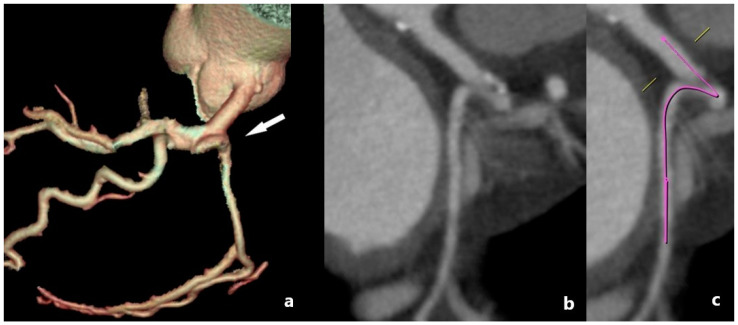

冠状动脉可在数量、起始点或路线上变化。这些变异属于冠状动脉解剖变异/异常的范畴,代表冠状动脉血管系统的先天性异常。通常,它们是良性的,无症状的,并且在为其他适应症进行冠状动脉造影时无意中被发现。然而,在某些情况下,异常的特征或其与周围结构的相互作用可能导致血流动力学紊乱。这些紊乱会导致血流紊乱,进而增加动脉粥样硬化和心肌缺血的可能性。如果有症状,潜在的表现包括胸痛、心律失常、晕厥、心肌梗死和心源性猝死。鉴于在某些情况下可能危及生命的并发症,早期和准确的诊断冠状动脉异常是至关重要的。用于评估冠状血管的最常用的诊断程序是冠状血管造影和多探测器行计算机断层扫描(MDCT)冠状血管造影。多层螺旋ct血管造影是一种无创、可靠、安全、灵敏的冠状动脉详细解剖可视化方法。它提供高分辨率成像,能够精确评估先天性冠状动脉变异,有助于临床决策和长期患者管理。我们进行了一项叙述性的回顾,分析和整合了大量关于冠状动脉变异和异常的文献。我们的目的是提供一个全面的,尽管不是详尽的,关于其定义、分类和MDCT血管造影检测的基本概念和发现的概述。通过整合MDCT成像的现有知识,我们寻求更好地理解冠状动脉变异的临床意义及其在心血管健康中的作用。

Coronary arteries may vary in quantity, point of origin, or course. These variations fall under the category of anatomical variants/anomalies of the coronary arteries, representing congenital abnormalities of the coronary vascular system. Generally, they are benign, asymptomatic, and identified inadvertently during coronary angiography conducted for alternative indications. However, in some cases, the anomaly's characteristics or its interaction with surrounding structures may cause hemodynamic disturbances. These disturbances can lead to turbulent blood flow, which in turn poses an increased likelihood for the development of atherosclerosis and myocardial ischemia. If symptomatic, potential manifestations include chest pain, arrhythmias, syncope, myocardial infarction, and sudden cardiac death. Given the potential for life-threatening complications in certain cases, the early and accurate diagnosis of coronary artery anomalies is of paramount importance. The most common diagnostic procedures used for the evaluation of coronary vessels are coronary angiography and multi-detector row computed tomography (MDCT) coronary angiography. MDCT angiography is a non-invasive, dependable, safe, and sensitive method for the detailed visualization of coronary anatomy. It offers high-resolution imaging that enables precise assessment of congenital coronary variations, aiding in both clinical decision-making and long-term patient management. We conducted a narrative review to analyze and integrate the body of literature on coronary artery varieties and anomalies. Our objective was to provide a comprehensive, albeit non-exhaustive, overview of essential concepts and findings related to their definition, classification, and detection with MDCT angiography. By integrating current knowledge in MDCT imaging, we seek to contribute to a better understanding of the clinical implications of coronary artery variations and their role in cardiovascular health.